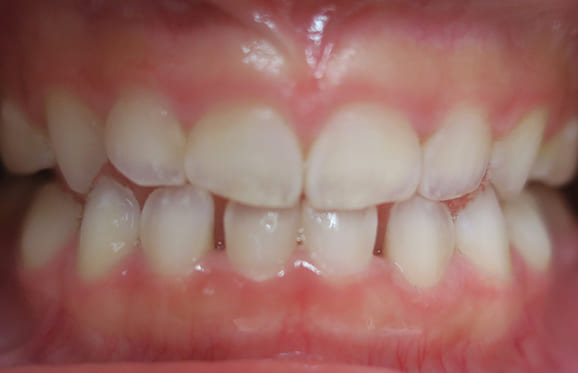

● 歯根が折れ保存不可の歯を抜歯して、そのスペースに八重歯を並べた症例

藤沢デンタルオフィスの虫歯や破折で抜歯後の部分矯正